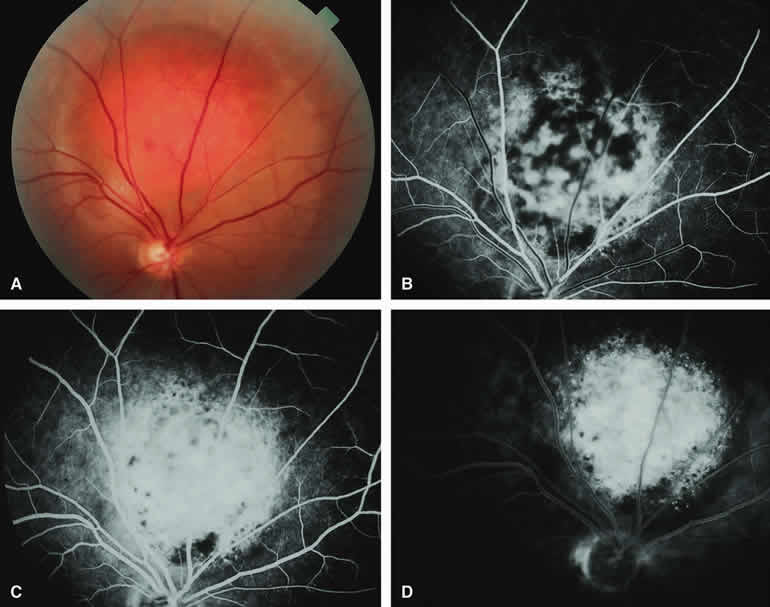

Choroidal Nevus Versus Melanoma with Prominent Lipofuscin Pigment Clumps

If one obtains a fluorescein angiogram on a small melanotic choroidal lesion (nevus versus melanoma) that has prominent clumps of lipofuscin pigment on its surface (Fig. 6), the pigment clumps appear intensely hypofluorescent throughout the study. This appearance is attributable to the complete blocking of choroidal fluorescence by the lipofuscin. ICG angiography does not show lipofuscin pigment clumps on the surface of the tumor as well as fluorescein angiography does.